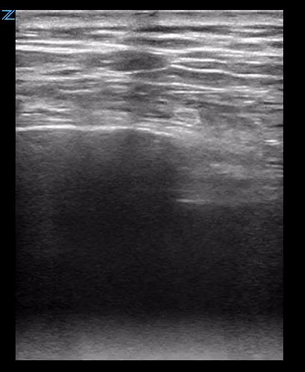

After a few minutes of squinting at the xray above, you realize it would take me a lot less time to simply ultrasound this patient’s ribs than it’s taking to interpret the image. So you get take the US with you as you go in for your initial evaluation and you get the images below.

Rib ultrasound is fairly simple. Ask where the patient is having the most pain, place the linear probe on top of and parallel to the rib(s) in that area. Identify the hyperechoic cortex and the rib shadowing below, the follow the cortex along the longitudinal path of the rib looking for distributions in the cortex.

The key is to remember that the ribs are obliquely oriented so when placing your probe on the patient you will need to angle it so it stays parallel to the path of the ribs, otherwise you may only catch slices of the bone and not see the full line of the cortex as above. If you’re having trouble identifying the ribs particularly in patients with a large amount of soft tissue, it can be helpful to place the probe sagittally and mark where you see each rib then reorient transversely to follow each rib longitudinally.